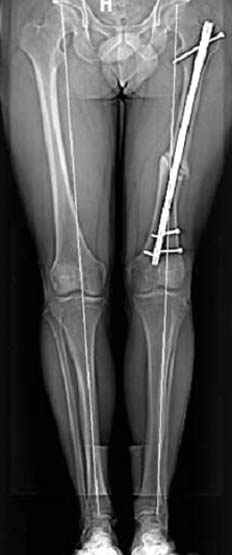

Несколько снимков из моей коллекции, чтобы разьяснить, почему мы до сих пор делаем различные варианты остеотомии.

На рисунке N1 предоперационный план лечения ложного сустава шейки бедра- линия ложного сустава, угол и направление введения импланта, клиновидная остеотомия в градусах и миллиметрах, второй снимок после коррекции, расчет, на сколько удлиняется конечность и размеры импланта;

N3 рисунок окончательный снимок, после операции моя рентгенограмма должен выглядеть примерно как эта картина. На N4 снимке клин перед удалением; N5 послеоперации 3 нед.; N6 окончательная рентгенограмма.

Интересно бы посмотреть рентгенограмму таза (оба сустава) а также рентгенгорамму с захватом коленных суставов (по Dror Paley).